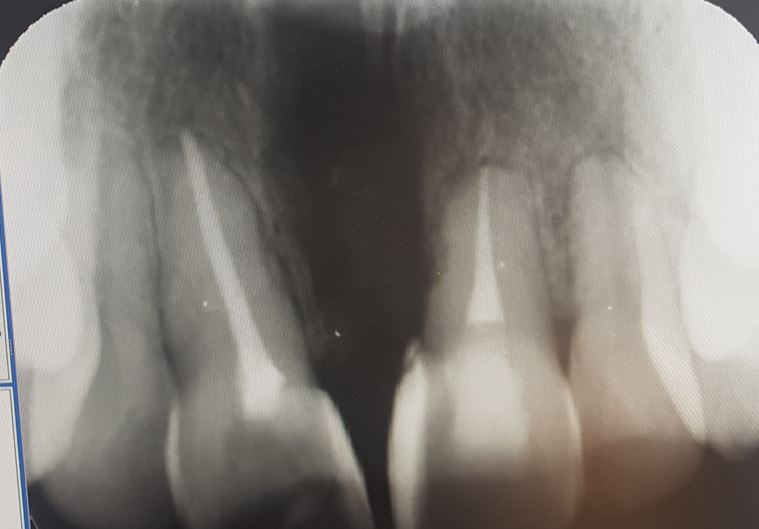

Ik ga proberen het redelijk kort te houden omdat de situatie al sinds 2017 speelt. Ik ben 36 en heb een groot botdefect tussen mijn voortanden.

Het is beginnen door een sarpe, kaakverbredende operatie. Het bot tussen mijn voortanden is niet teruggegroeid. De ortho heeft dit niet opgemerkt en is 3 jaar lang bezig geweest met het sluiten van de voortanden. Hierdoor heb ik een wortelkanaalbehandeling moeten laten doen aan 1 voortand, die andere was al door een val vroeger behandeld.

Zie foto voor de röntgen, ik kan ook wel een foto van de huidige situatie posten maar het is een vrij grafisch beeld...

De zorgverzekeraar heeft toch een gedeelte van de behandeling vergoed gelukkig. Er is gisteren een foto gemaakt waarop nieuwe botaangroei is te zien, een stuk beter dan de foto in de openingspost. Nu ligt het kaakbot nog zo'n 4,5 mm hoger dan de lijn bij de andere tanden dus de voortanden zijn nu stabiel. Van het tandvlees is wel veel verloren gegaan, waarschijnlijk is de enige optie een rotatieflap van het gehemelte. Maar de kaakchirurg adviseerde mij dit pas te doen als aller laatste optie. Het geeft een grote wond in het gehemelte en de procedure wordt kennelijk niet heel vaak uitgevoerd. Waarschijnlijk ga ik voor nu voor een esthetische correctie dmv facings of kronen waar met roze composiet toch iets verbloemd kan worden, maar daarvoor moet ik naar andere specialisten.